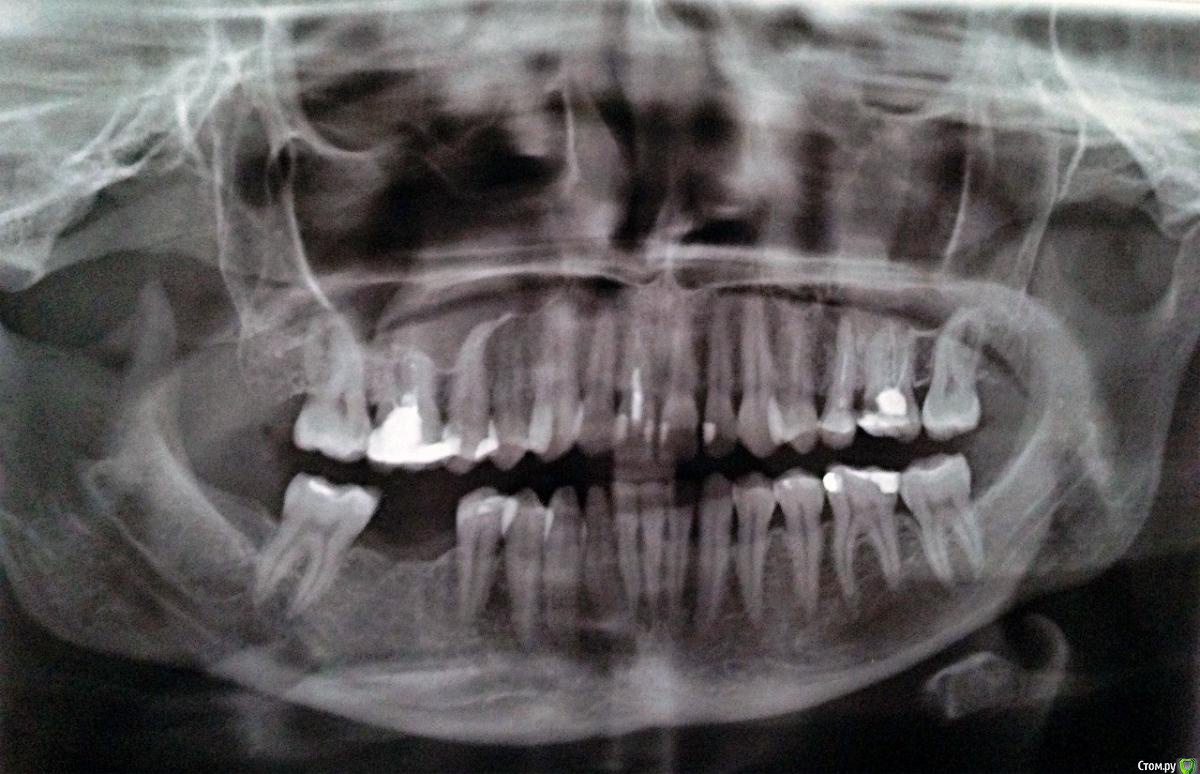

katrin12098 Опубликовано 15 августа, 2015 Поделиться Опубликовано 15 августа, 2015 (изменено) Здравствуйте!Подскажите пожалуйста.Заболела верхняя пятерка,пошла на прием к стоматологу сделали снимок сказали киста и нужно удалять в стационаре,так как зуб находиться рядом с гайморовой пазухой в поликлинике удалять отказались. Пропила пять дней амоксиклав зуб перестал беспокоить, насколько велика вероятность перфорации гайморовой пазухи и возможно ли удалить в клинике или всё же лучше обратиться в больницу в челюстно лицевую хирургию и удалить там? и какие могут быть осложнения? и возможно ли сохранить зуб? Изменено 15 августа, 2015 пользователем katrin12098 Ссылка на комментарий

St. Опубликовано 16 августа, 2015 Поделиться Опубликовано 16 августа, 2015 Верхние пятый и шестой можно попробовать перелечить каналы и наблюдать. Если там нет трещин большая вероятность, что воспаление после качественной эндодонтии пройдет.Верхний шестой справа и центральный резец справа тоже необходимо перелечить каналы. И подумать о имплантации в области отсутствующего на нижней челюсти. Ссылка на комментарий

katrin12098 Опубликовано 19 августа, 2015 Автор Поделиться Опубликовано 19 августа, 2015 (изменено) Верхнюю пятерку решила удалять.подскажите что делать с шестым верхним?также интересует правая сторона пятый и шестой верхний зуб.возможна ли имплантация шестого нижнего и нужен ли костный блок? Изменено 19 августа, 2015 пользователем katrin12098 Ссылка на комментарий